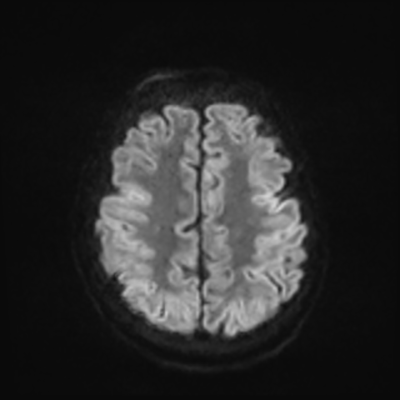

MRI brain (DWI)

MRI brain (DWI) 1/24 1/24

You can clearly see diffuse cortical and basal ganglia diffusion restriction, and that of his deep cerebellar nuclei as well. The right occipital lobe abnormalities are a little more prominent, but then you remember that he is known to have had a right occipital stroke weeks ago.

In reviewing his data, you know that he doesn't have any of the strong predictors of a poor neurologic prognosis. However, based on these findings on MRI, along with the absent reactivity on cEEG, you are able to tell the primary team and the patient's family that he is likely to have a poor prognosis, based on these multiple moderate predictors. Recovery is not completely impossible-- there is more uncertainty with this prognostication than if we were able to get SSEPs-- but you're very worried about his outlook and that any potential recovery would require a very protracted rehabilitation period. Given his high cervical cord injury level, tracheostomy would be required anyway. So, it comes down to whether his family thinks he'd want to pursue these aggressive measures.